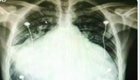

男子心脏如足球大 被取"瘦身"